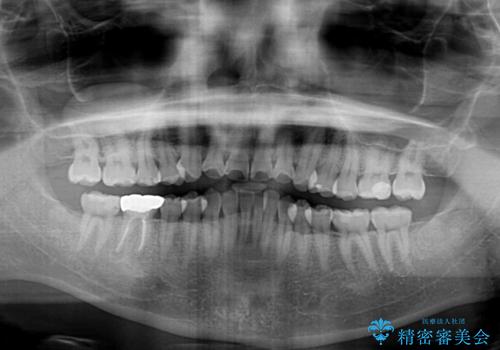

- 前歯のデコボコを治したいとのことで来院された患者様です。

できる限り楽して、短期間で治したいとのことで、ワイヤー装置にて矯正治療を行うこととしました。